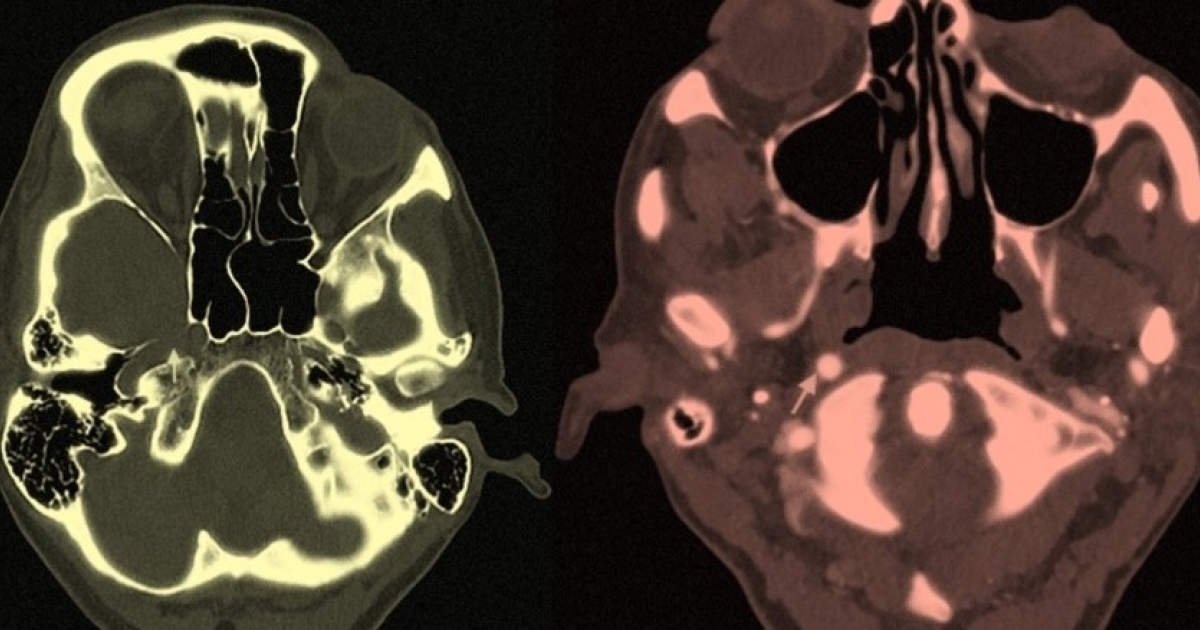

Инсульт позволил обнаружить отсутствие внутренней сонной артерии у британки.

Инсульт позволил обнаружить отсутствие внутренней сонной артерии у британки. Инсульт позволил обнаружить отсутствие внутренней сонной артерии у британки